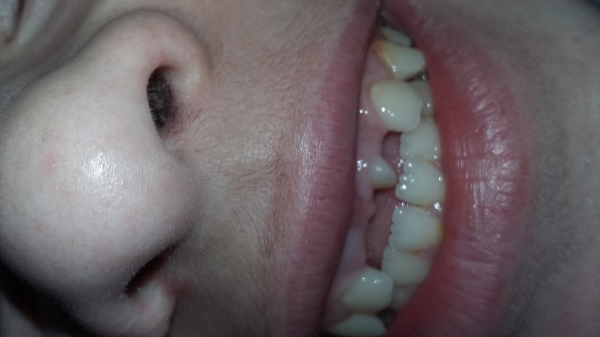

У моего ребенка выпали зубы передние верхние уже как 2,5 года. Новые зубы не растут. Один зуб вылез и тот поперек и на половину, и остановился в росте.

Ребенку уже 12 лет, а он без зубов. Снимок делали, зубы есть. Все остальные зубы вылезли один за другим, а вот с передними проблема.

Что делать с зубом, который вылез неправильно? Он может развернуться сам со временем или нет? Что делать?